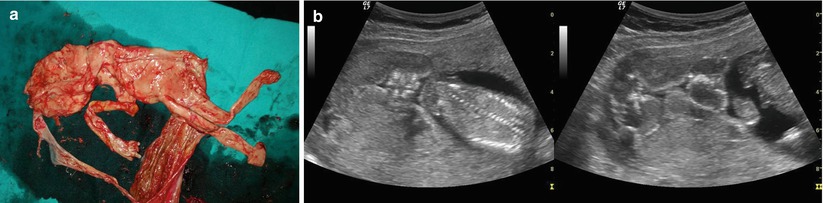

Twin Pregnancies Obgyn Key Clinicians and women should be aware that monochorionic twin pregnancies have higher fetal loss (miscarriage, stillbirth, and neonatal death) rates than dichorionic twin pregnancies, and overall may have a higher risk of associated neurodevelopmental morbidity. Learn how twin pregnancies differ from singleton pregnancies, and what that means for office visits, nutrition, and recommended screenings. To review current international clinical guidelines on the antenatal and intrapartum management of twin pregnancies, examining areas of consensus and conflict. we conducted a database search using medline, pubmed, scopus, academic search complete, cinahl and erci guidelines website. Women with a twin pregnancy should be cared for by an experienced multidisciplinary team in a specialized twin clinic.6 twins that develop complications, and all monochorionic monoamniotic twins, should be referred to a tertiary center.

Twin Pregnancies Obgyn Key To review current international clinical guidelines on the antenatal and intrapartum management of twin pregnancies, examining areas of consensus and conflict. we conducted a database search using medline, pubmed, scopus, academic search complete, cinahl and erci guidelines website. Women with a twin pregnancy should be cared for by an experienced multidisciplinary team in a specialized twin clinic.6 twins that develop complications, and all monochorionic monoamniotic twins, should be referred to a tertiary center. This guideline reviews the evidence based management of normal and complicated monochorionic twin pregnancies. To review current international clinical guidelines on the antenatal and intrapartum management of twin pregnancies, examining areas of consensus and conflict. Accurate dating and determination of chorionicity is critical in the management of twin pregnancies. structural anomalies, placental abnormalities, cervical shortening, and fetal growth disturbances are all more common in twins. These documents provide recommendations on antenatal surveillance and management of twin pregnancies. at the same time, these guidelines identify several key areas where evidence is limited and additional research is needed.

Twin Pregnancies Obgyn Key This guideline reviews the evidence based management of normal and complicated monochorionic twin pregnancies. To review current international clinical guidelines on the antenatal and intrapartum management of twin pregnancies, examining areas of consensus and conflict. Accurate dating and determination of chorionicity is critical in the management of twin pregnancies. structural anomalies, placental abnormalities, cervical shortening, and fetal growth disturbances are all more common in twins. These documents provide recommendations on antenatal surveillance and management of twin pregnancies. at the same time, these guidelines identify several key areas where evidence is limited and additional research is needed.